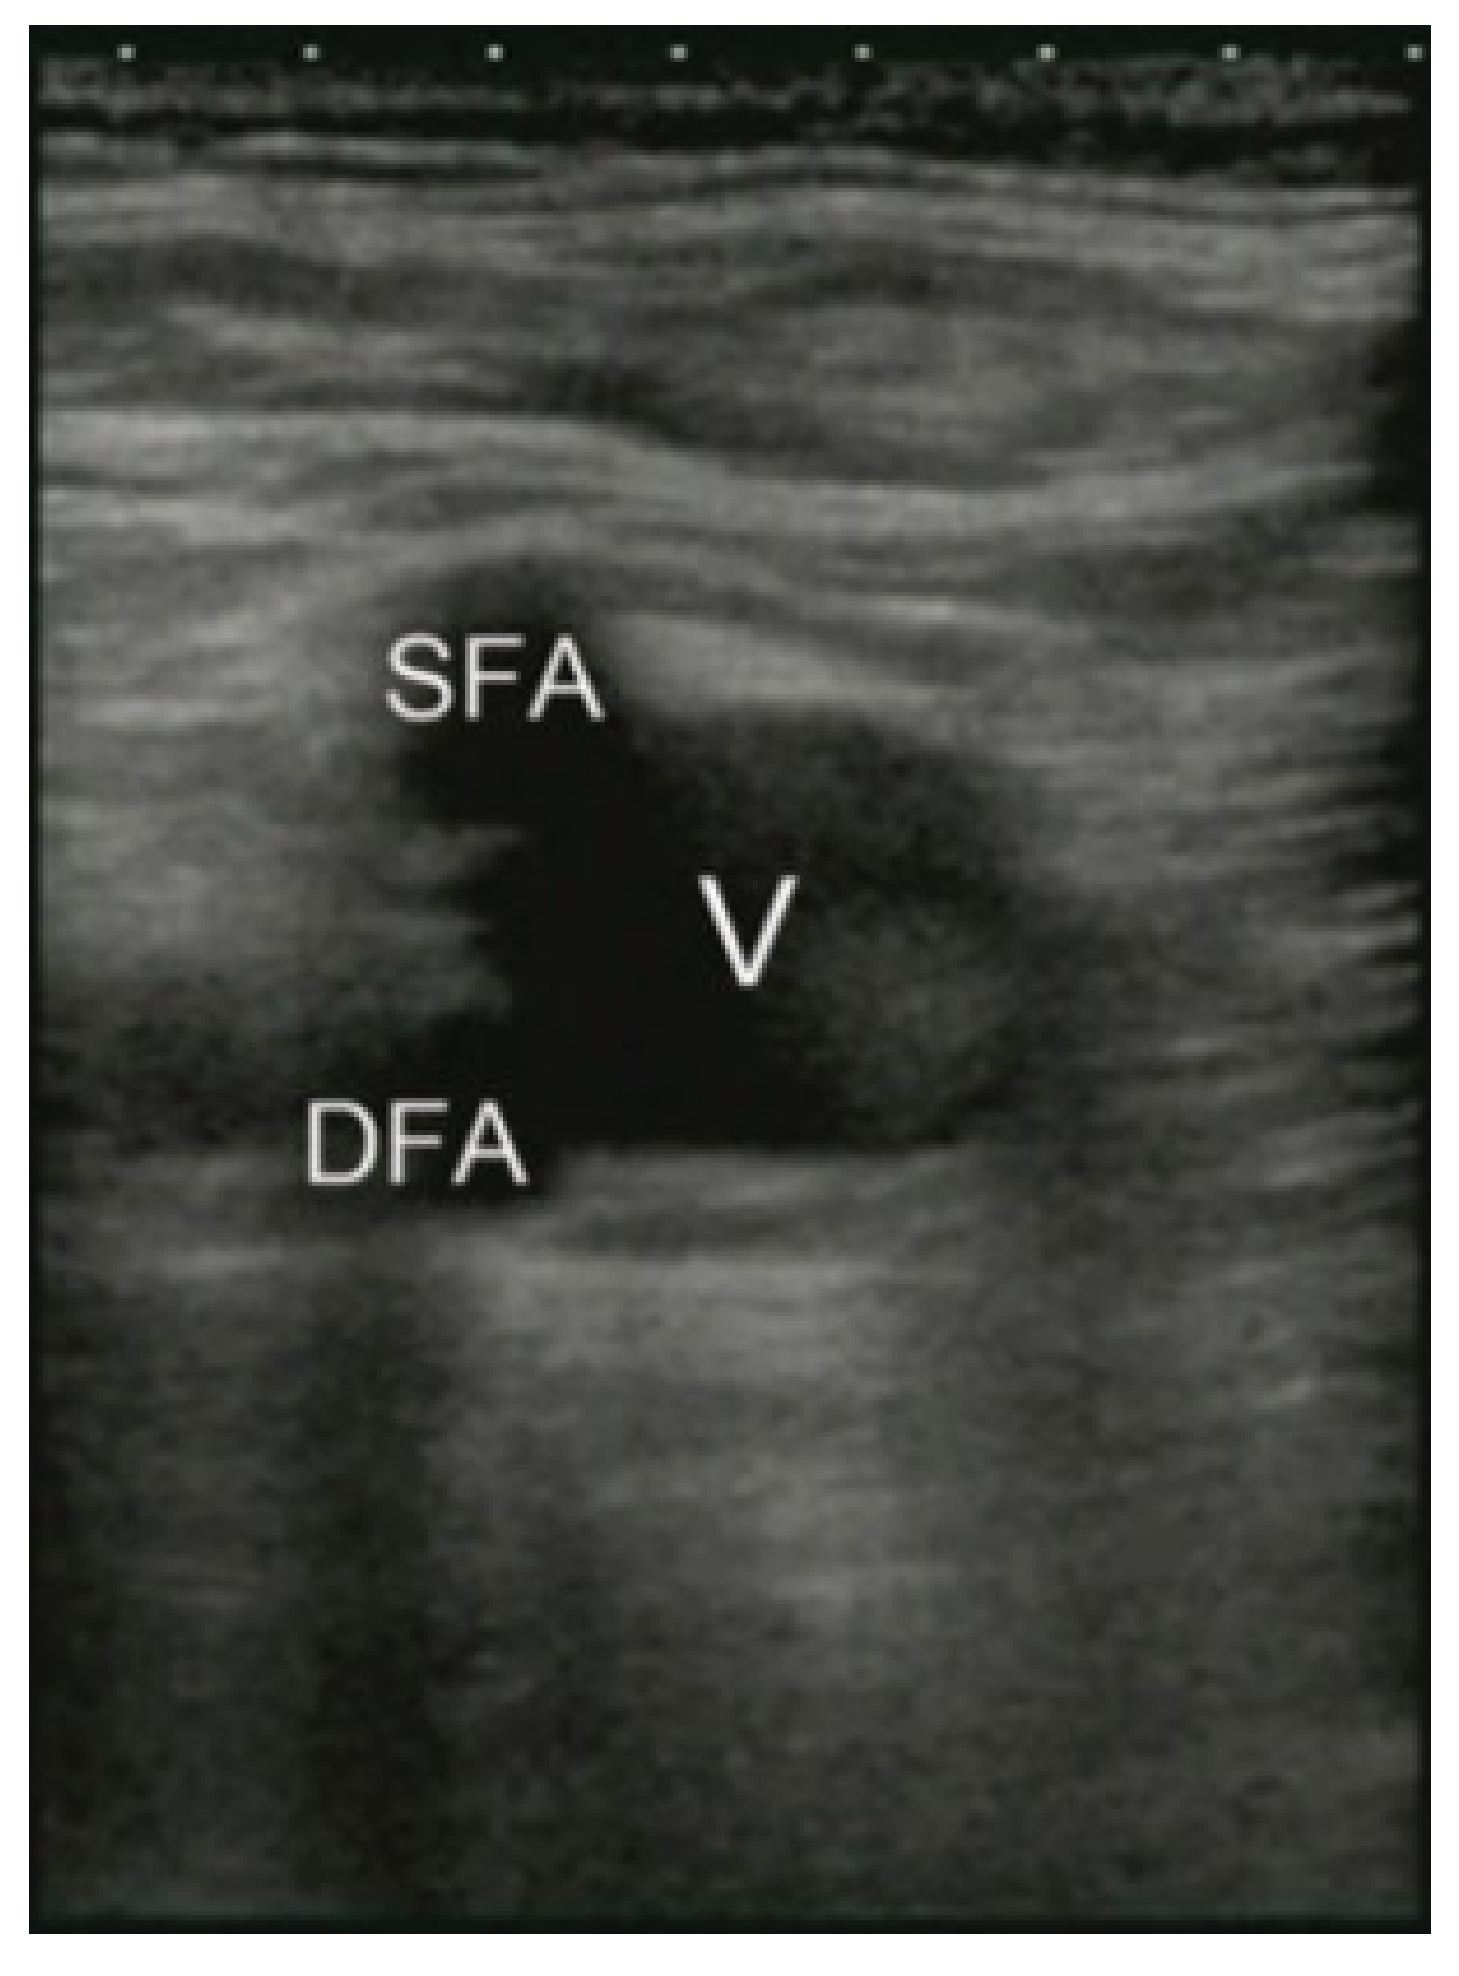

2.3. Access Points